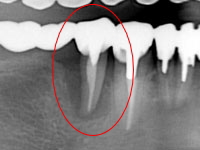

歯周組織の状態を調べるために、歯周ポケットの深さを計ったり、レントゲンを撮ったり、その他治療に必要な検査を行います。エムドゲインゲルを使った治療が行えるかどうがは、歯周病の程度や患者さんの健康状態によっても異なります。

手術は麻酔をかけますので、痛みはありません。まず最初に治療する部分の歯肉を切開し剥離します。歯根の表面の清掃を行いエムドゲインゲルを塗布します。最初に切開した歯肉部分を縫合し、終了です手術後はゆっくりご自宅で休んで頂き、後日感染を防ぐため消毒します。安定したら抜糸します。